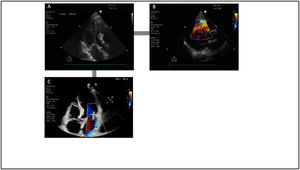

Ecocardiografía básicaLa ecografía inicial debe llevarse a cabo durante la fase de identificación lo más pronto posible. Esto permitirá realizar una evaluación básica de la contractilidad ventricular izquierda y derecha, respaldando o descartando el diagnóstico de SC. Además, ayudará a identificar etiologías potencialmente mortales del shock, como el taponamiento cardíaco (fig. 2)5.

Utilidad de la ecocardiografía en el shock cardiogénico. Cálculo del gasto cardíaco mediante la fórmula volumen sistólico=área del tracto de salida del ventrículo izquierdo×integral velocidad tiempo del tracto de salida del ventrículo izquierdo. Evaluación de la función ventricular izquierda y derecha, así como análisis de las presiones de llenado y presión de arteria pulmonar mediante Doppler pulsado del flujo transmitral en relación al estudio mediante Doppler tisular del anillo mitral.

La fracción de eyección del ventrículo izquierdo (FEVI) constituye el método más empleado en la práctica clínica para valorar la función ventricular izquierda. Esta medida proporciona una evaluación cuantitativa de la función sistólica global del VI. No obstante, es crucial tener presente que la FEVI es un parámetro sumamente influenciado por factores como la precarga y la poscarga. Estos factores pueden distorsionar la interpretación de la FEVI y deben ser considerados cuidadosamente al utilizarla como herramienta diagnóstica y pronóstica en pacientes con SC60.

En este punto, la ecocardiografía también es útil para valorar las alteraciones segmentarias de la contractilidad, información crucial, ya que sugiere la presencia de un síndrome coronario agudo como causa subyacente61.

Respecto a la función del VD, además de valorar el tamaño con relación al VI, un parámetro básico que nos permite estimar la función sistólica es la excursión del plano del anillo tricuspídeo (TAPSE). Medido en el plano apical 4 cámaras, calcula el grado de desplazamiento longitudinal del segmento anular del VD desde telediástole hasta el pico sistólico. Un valor <17mm sugiere disfunción sistólica del VD62.

Asimismo, en esta fase se debería descartar la existencia de patología valvular grave o taponamiento cardiaco63.

Evaluación de la función ventricular izquierdaLa ecocardiografía puede estimar de manera no invasiva el volumen sistólico mediante el estudio con Doppler pulsado del tracto de salida del ventrículo izquierdo (TSVI)64, siendo útil para monitorizar la respuesta a los tratamientos65. Se mide mediante el producto del área de sección transversal del TSVI con la integral de velocidad-tiempo (IVT) del flujo aórtico en el TSVI (fig. 2). La evaluación única de la IVT se ha tomado como sustituto del GC y se ha utilizado con éxito, especialmente en la cuantificación de la respuesta a volumen6. Asimismo, la ecocardiografía permite medir de forma no invasiva el CP36.

Por último, el análisis ecocardiográfico mediante Doppler tisular de la onda sistólica del anillo mitral o mediante el strain miocárdico podría representar un parámetro más fiable en comparación con la FEVI, siendo capaz de identificar cambios miocárdicos más tempranos y pequeños, representando un buen predictor del pronóstico temprano en pacientes con SC complicando un IAM66.

Evaluación de la función diastólicaLa ecocardiografía permite el estudio de la función diastólica y de las presiones de llenado mediante el estudio con Doppler pulsado del flujo transmital (onda E) y tisular del anillo mitral (onda e’)67,68 (fig. 2). Considerando la ratio E/e’ se puede hacer una aproximación a las presiones de llenado del VI, de forma que valores de E/e’>14 estiman presiones capilares pulmonares elevadas y E/e’<8 estiman presiones normales69. En un reciente estudio retrospectivo se mostró que varios parámetros ecocardiográficos (incluyendo índice de volumen sistólico bajo y una relación E/e’ elevada) se correlacionaron con la clasificación SCAI del SC y la mortalidad70.

Evaluación de la función ventricular derechaLa ecuación de Bernoulli simplificada permite calcular el gradiente de presión entre la aurícula y el ventrículo derecho mediante el uso del Doppler continuo en el trazado de la regurgitación tricuspídea. Al incorporar la PAD, este cálculo proporciona una estimación de la presión arterial sistólica de arteria pulmonar (PAPs).

Para el estudio de la función sistólica del VD, además del TAPSE, cuyas principales limitaciones son la dependencia de la carga, una reducción en el contexto de fibrilación auricular y los casos de disfunción regional, podemos optar por parámetros como la onda sistólica del Doppler tisular del anillo tricúspideo o el cambio de área fraccional (fig. 2).